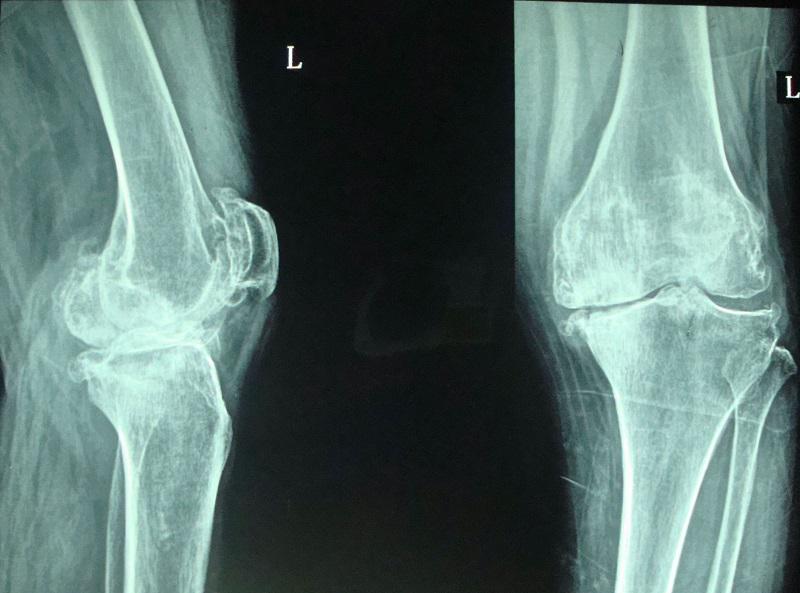

上下楼梯膝关节疼痛的原因 上下楼梯时,膝关节需要承受的压力更多,关节屈曲的角度较大(如下图1所示),大骨腿与小腿骨之间的接触面较小;髌骨承担“支点”的作用,并在负重的情况下滑动。骨与骨之间的作用力大幅增加。